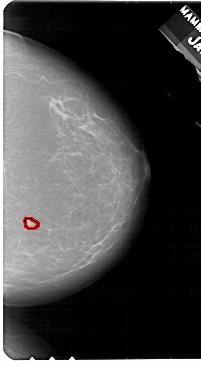

A_1943_1.LEFT_MLO

LEFT_MLO LINES 5491 PIXELS_PER_LINE 3361 BITS_PER_PIXEL 12 RESOLUTION 43.5 NON_OVERLAY

FILE: A_1943_1.RIGHT_MLO.OVERLAY

TOTAL_ABNORMALITIES 1

ABNORMALITY 1

LESION_TYPE MASS SHAPE LOBULATED MARGINS ILL_DEFINED

ASSESSMENT 3

SUBTLETY 3

PATHOLOGY BENIGN

TOTAL_OUTLINES 1

BOUNDARY